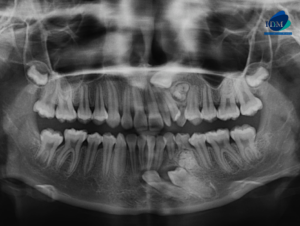

Paciente femenino de 39 años de edad, es referido al Instituto de Diagnóstico Maxilofacial – IDM para evaluación general.En la radiografía panorámica (Figura 1), se